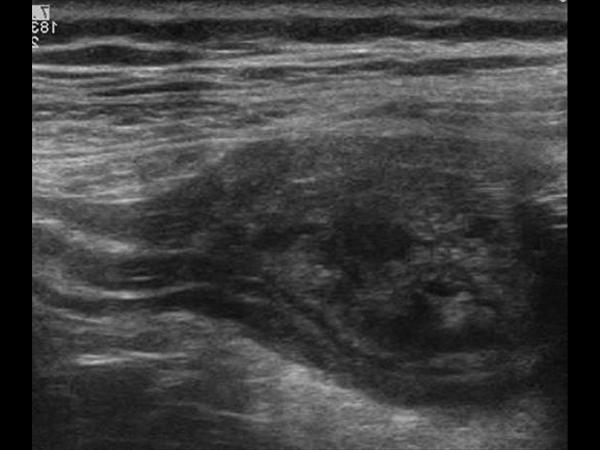

Mucocele ruột thừa

» Thông tin: Nam giới – 71 tuổi.

» Lâm sàng: Đau hố chậu phải mạn tính.